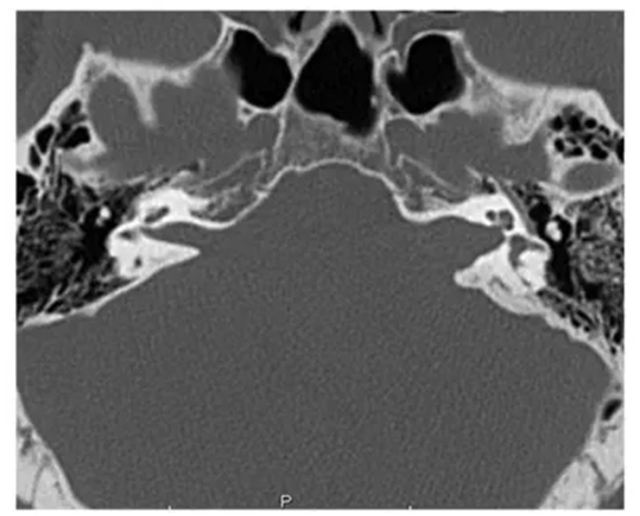

CT可清晰显示颞骨、内听道的骨性结构,能为手术方式选择提供参考。